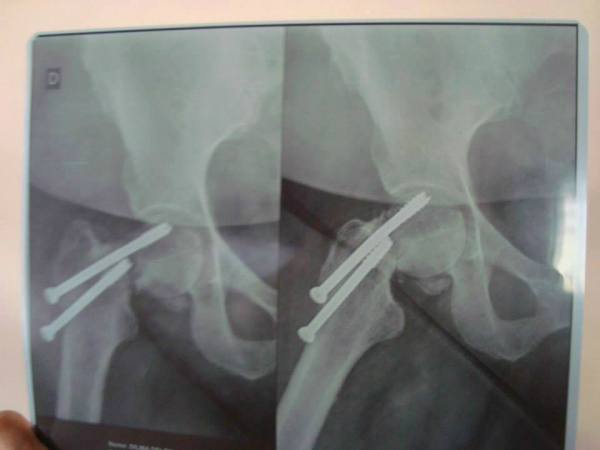

Dill sofreu um acidente de moto no dia 25 de maio, segundo ela foi bem atendida pelos médicos do SAMU (Serviço de Atendimento Móvel de Urgência) e que o primeiro médico que a atendeu disse que ela necessitaria de uma cirurgia pois havia quebrado o Fêmur, esse médico também disse que a paciente seria enviada para Campo Grande para tal procedimento.

Porém, ao acordar Dilma foi atendida por um segundo médico que a informou que ele mesmo faria a cirurgia citada no primeiro momento, crente da solução resolvida, a mulher foi para mesa de cirurgia no domingo dia 26 de maio. Depois 40 dias de repouso e dores a paciente voltou ao ortopedista para reavaliação e soube pelo médico que a cirurgia não havia dado certo e que deveria colocar uma prótese.